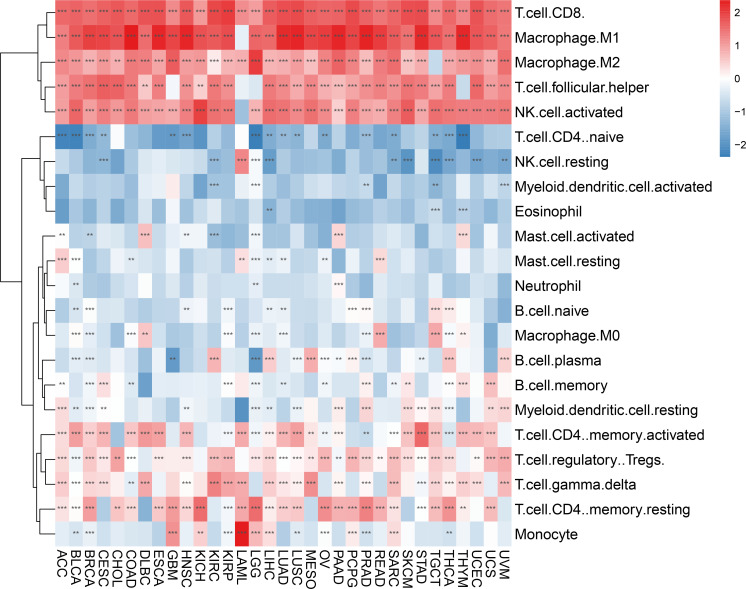

We evaluated 33 different types of tumors for determining associations between IFN-γ score and discovered a positive link between IFN-γ and M1 and M2 Macrophages, T cells follicular helper cells, activated NK cells, and CD8 T cells in most cancers. Also, the IFN-γ score showed an inverse association with T cell CD4 naïve and NK cell resting. (f9). In the analysis of tumor immune score, the IFN-γ score was found to have a positive correlation with the degree of immune cell infiltration in most of the 33 tumors studied (P < 0. 05, f10, Supplementary Figure 7). For PCPG, LUSC, PAAD, SARC, READ, KIRP, COAD, GBM, UCS, KICH, THYM, CHOL, LGG, and ACC, IFN-γ score was positively linked to stromal cell score (f10). Additionally, the IFN-γ score had a positive link to the TME score of ACC, SKCM, UVM, THCA, SARC, UCS, KIRC, LGG, KIRP, TGCT, CESC, LIHC, BRCA, LUSC, KICH, LUAD, OV, LAML, READ, BLCA, MESO, HNSC, GBM, CHOL, COAD, UCEC, PAAD, PCPG, DLBC, PRAD, ESCA, STAD, and THYM (All P < 0. 05, f10). The above results indicate that IFN-γ is closely related to the immune status of tumors.